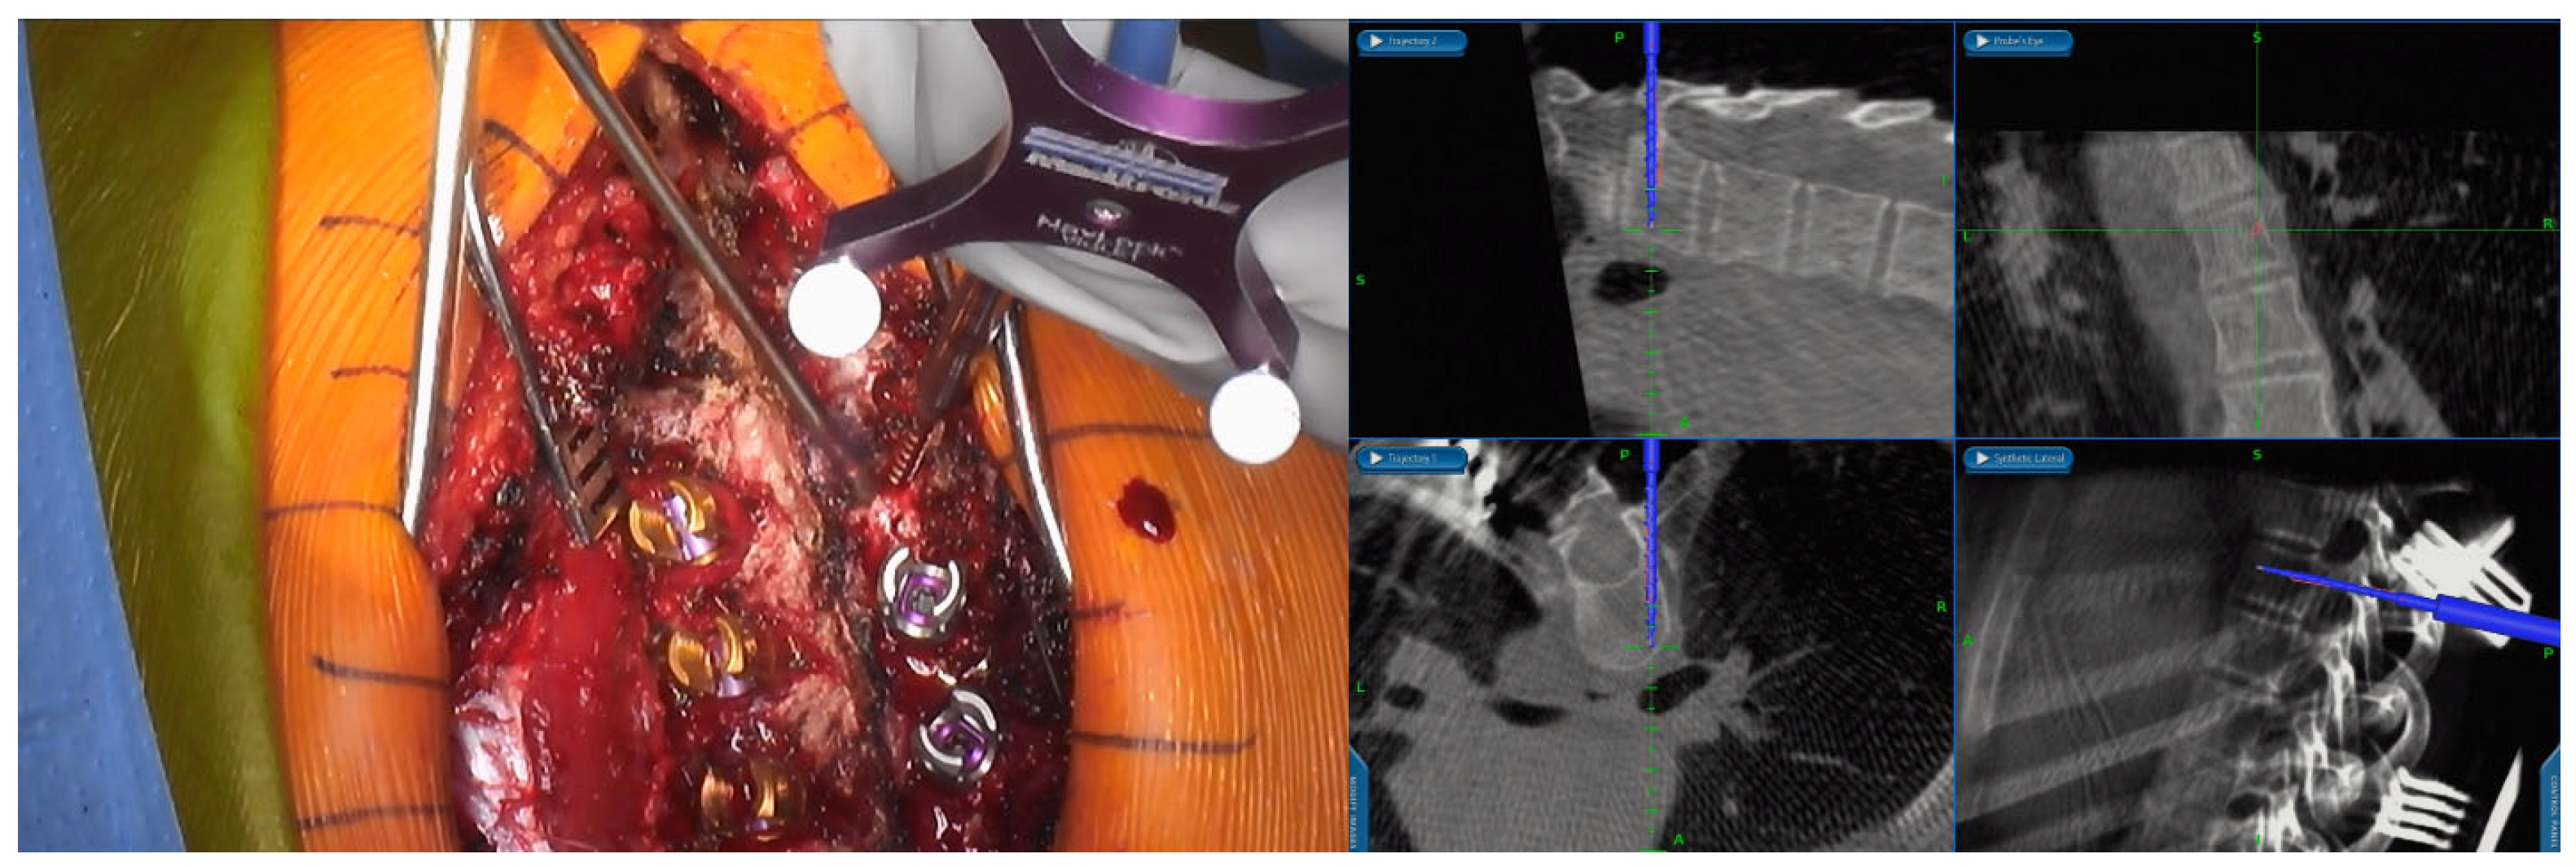

2.1. Screw Placement Workflow